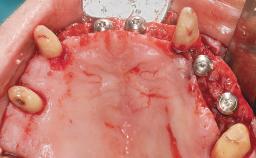

A 63-year-old male patient was referred for a consultation and treatment of partial edentulism in the maxilla. The patient presented with residual anterior teeth and declined a partial removable prosthesis. He reported that the maxillary posterior teeth had been extracted due to mobility and periodontal disease two months before the consultation. The patient’s chief complaint was that his residual maxillary teeth were mobile and that he was unable to chew. The patient’s desire was a stable and comfortable fixed maxillary rehabilitation. The patient was a light smoker (fewer than 10 cigarettes/ day), and his medical history was without significant findings. He was not on any regular medication at the time of consultation. The extraoral examination revealed a normal physiognomy with a correct distribution of the facial thirds. The patient presented a low lip line, and the transition line between teeth and soft tissues was not exposed during a forced smile.

| # of Implants | 6 |

| Bone Augmentation | Horizontal|Simultaneous |

| Augmentation Materials | Xenogenous |

| Modality | 6+ implants with immediate loading |